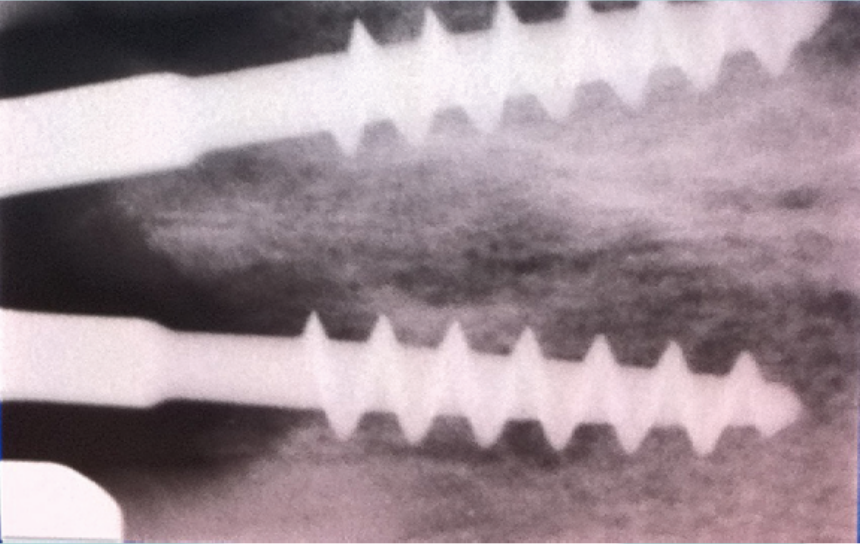

implantologia italiana Bazzoli

implantologia di scuola italiana studi dentistici Bazzoli e Bellini